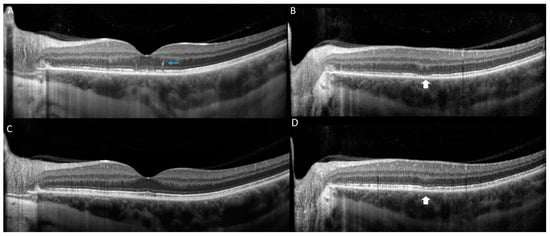

2. Case Report